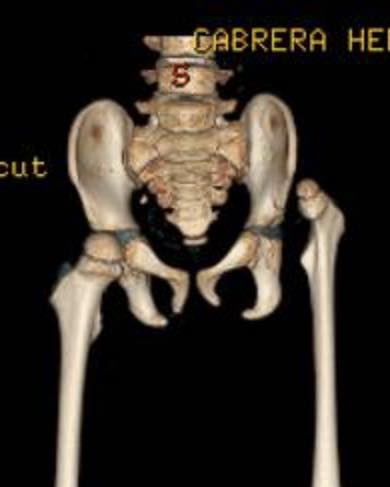

Atrogriposis con cadera luxada

Este superhéroe se llama Jesús Fernando y actualmente tiene cinco años. Nació con artrogriposis y con la cadera izquierda luxada. Recibió tratamiento en un hospital público, pero sin éxito; incluso la cirugía realizada fue fallida. Les comparto las fotografías de cómo llegó a mi consulta hace un año, y las imágenes después del tratamiento con yesos e intervenciones quirúrgicas: dos en los pies y una en la cadera. Mi valiente pacientito llegó sin poder caminar, ¡y ahora ya anda jugando por todos lados! Felicidades a sus papás por el esfuerzo para darle a Jesús Fernando este enorme regalo. Me siento muy agradecido por su confianza.